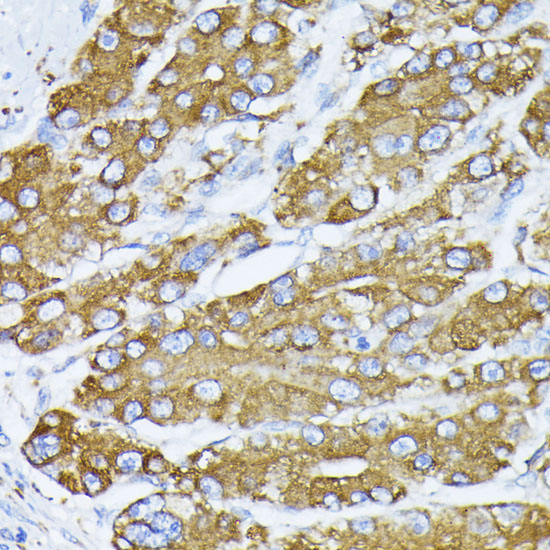

Immunohistochemistry of paraffin-embedded human liver cancer using BiP/GRP78 antibody.